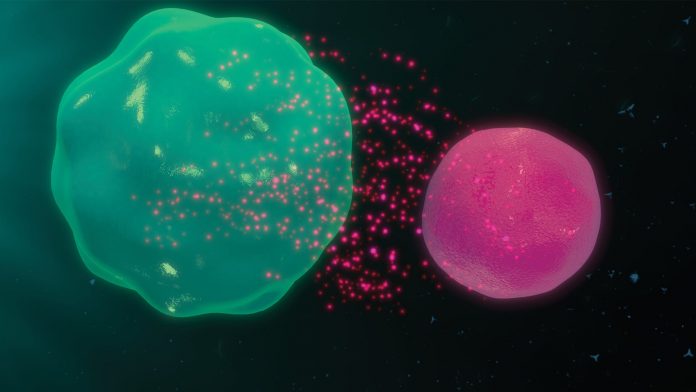

GvHD occurs in patients treated with allogeneic HSCT through co-transplantation of allo-reactive T cells. These T cells are activated by antigen-presenting cells and induce tissue damage in the skin, gut and liver. GvHD and autoimmune diseases share clinical and pathophysiological similarities, as aberrantly activated T cells play a central role in both diseases.

T-Guard represents a novel concept for addressing unwanted activities of the immune system. T-Guard is an antibody-based combination product candidate that has the potential to swiftly and safely remove hyper-reactive or misdirected T cells in patients suffering from various T cell-mediated diseases, as well as transplant-related rejection.

The novelty of T-Guard lies in the use of a combination of two immunotoxins that act synergistically to kill target cells. The product consists of two monoclonal antibodies (mAbs), directed against T cell surface antigens CD3 and CD7, which are both individually conjugated to ricin toxin A (RTA).

T-Guard is highly specific in killing only the activated T cells; the immunotoxin used in T-Guard contains only the A chain of the highly effective ricin toxin. The ricin toxin B chain (RTB) normally accommodates the binding and subsequent internalisation of RTA into eukaryotic cells, after which RTA irreversibly inhibits cellular proteins, leading to the cell’s death. By replacing RTB with a specific mAb, the resulting mAb-RTA conjugate binds to and eliminates only those cells that express the target antigen. Bystander cells are left unharmed as the crippled RTA toxin is not able to enter the cell on its own and needs the mAb as a transfer vehicle into the cell before it can exert its deleterious effect.